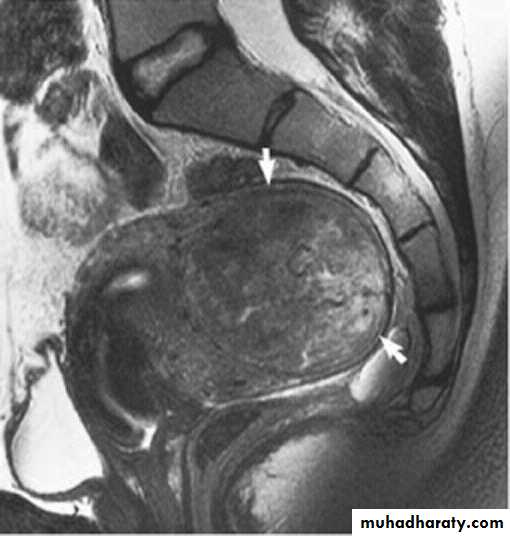

Sagittal coronal